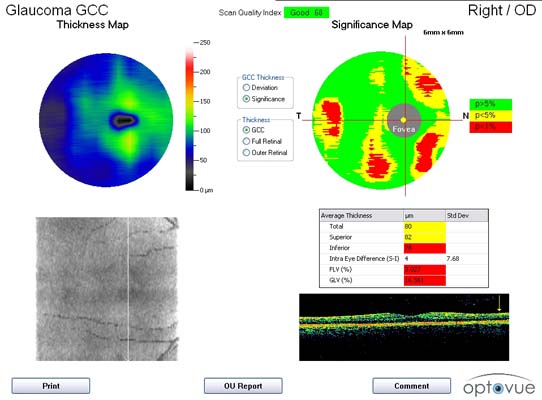

Glaukom - zobrazovací metody

Současné zobrazovací metody glaukomu považujeme za velmi přínosné pro stanovení diagnózy glaukomu a sledování vývoje onemocnění v čase. Těmito metodami sledujeme objektivně projevy glaukomové neuropatie včetně její progrese.